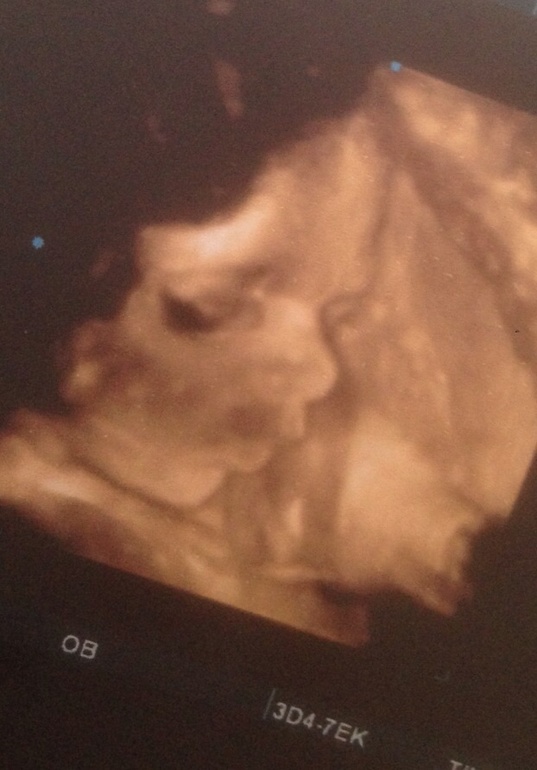

Вообщем дочурка развивается на две недели быстрее сверстников..уже 1800 кг,40 см...вот уж точно не ожидала)Просила её каждый день,милая,давай ты будешь килограмчика 3-.3.200 ))а потом мама тебе откормит..но она решила ,что маме нужно будет хорошенько постараться)))я все время мы с ножкой во рту))второй скрининг за этим наблюдаем!похожи мы на папулю)только губы мамины взяла..)я кончено понимаю,что все еще 100 раз поменяется,но на данный момент так)